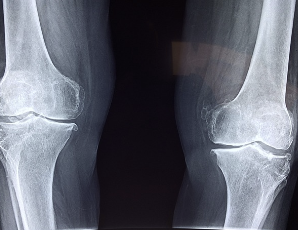

글루코사민 콘드로이친 msm 효능 및 부작용 적정섭취량 알아봐요 글루코사민 콘드로이친 msm 효능 및 부작용 적정섭취량 등 관련 정보 알아보도록 하겠습니다. 관절은 뼈와 뼈 사이에 위치한 연결점으로, 우리 몸을 움직이기 위한 중요한 부분입니다. 관절은 뼈의 끝에 위치한 연골과 뼈를 연결하는 인대로 이루어져 있으며, 이러한 구조는 원활한 움직임을 가능하게 합니다. 하지만 연령이 들어가거나 부상 등으로 인해 관절의 기능이 손상되면 관절염과 같은 질환으로 발생할 수 있습니다. 이러한 질환은 관절 통증, 감각 이상, 염증 및 손상 등을 일으키며, 일상생활에서의 움직임과 활동에 지장을 주어 생활의 질을 저하시킵니다. 이에 따라 적절한 치료와 예방이 필요하며, 영양소와 운동 등을 통한 관리가 중요합니다.

글루코사민은 연골을 유지하는 데 필요한 성분으로, 연골 조직의 생산과 수리를 돕습니다. 또한 관절염 등의 관절 질환으로 인한 통증 및 염증을 완화하는데도 효과적입니다. 또한 연골 조직의 건강을 유지함으로써, 무릎 퇴행성 질환의 발생을 예방하고 뼈 건강에도 도움을 줄 수 있습니다.

글루코사민의 효과는 개인차가 있으며, 꾸준한 섭취가 필요합니다. 또한, 이미 심각한 연골 손상이 발생한 경우에는 효과가 미미할 수 있으므로, 권장되는 운동량을 유지하고, 식이요법 및 다른 치료와 병행하여 사용하는 것이 좋습니다.